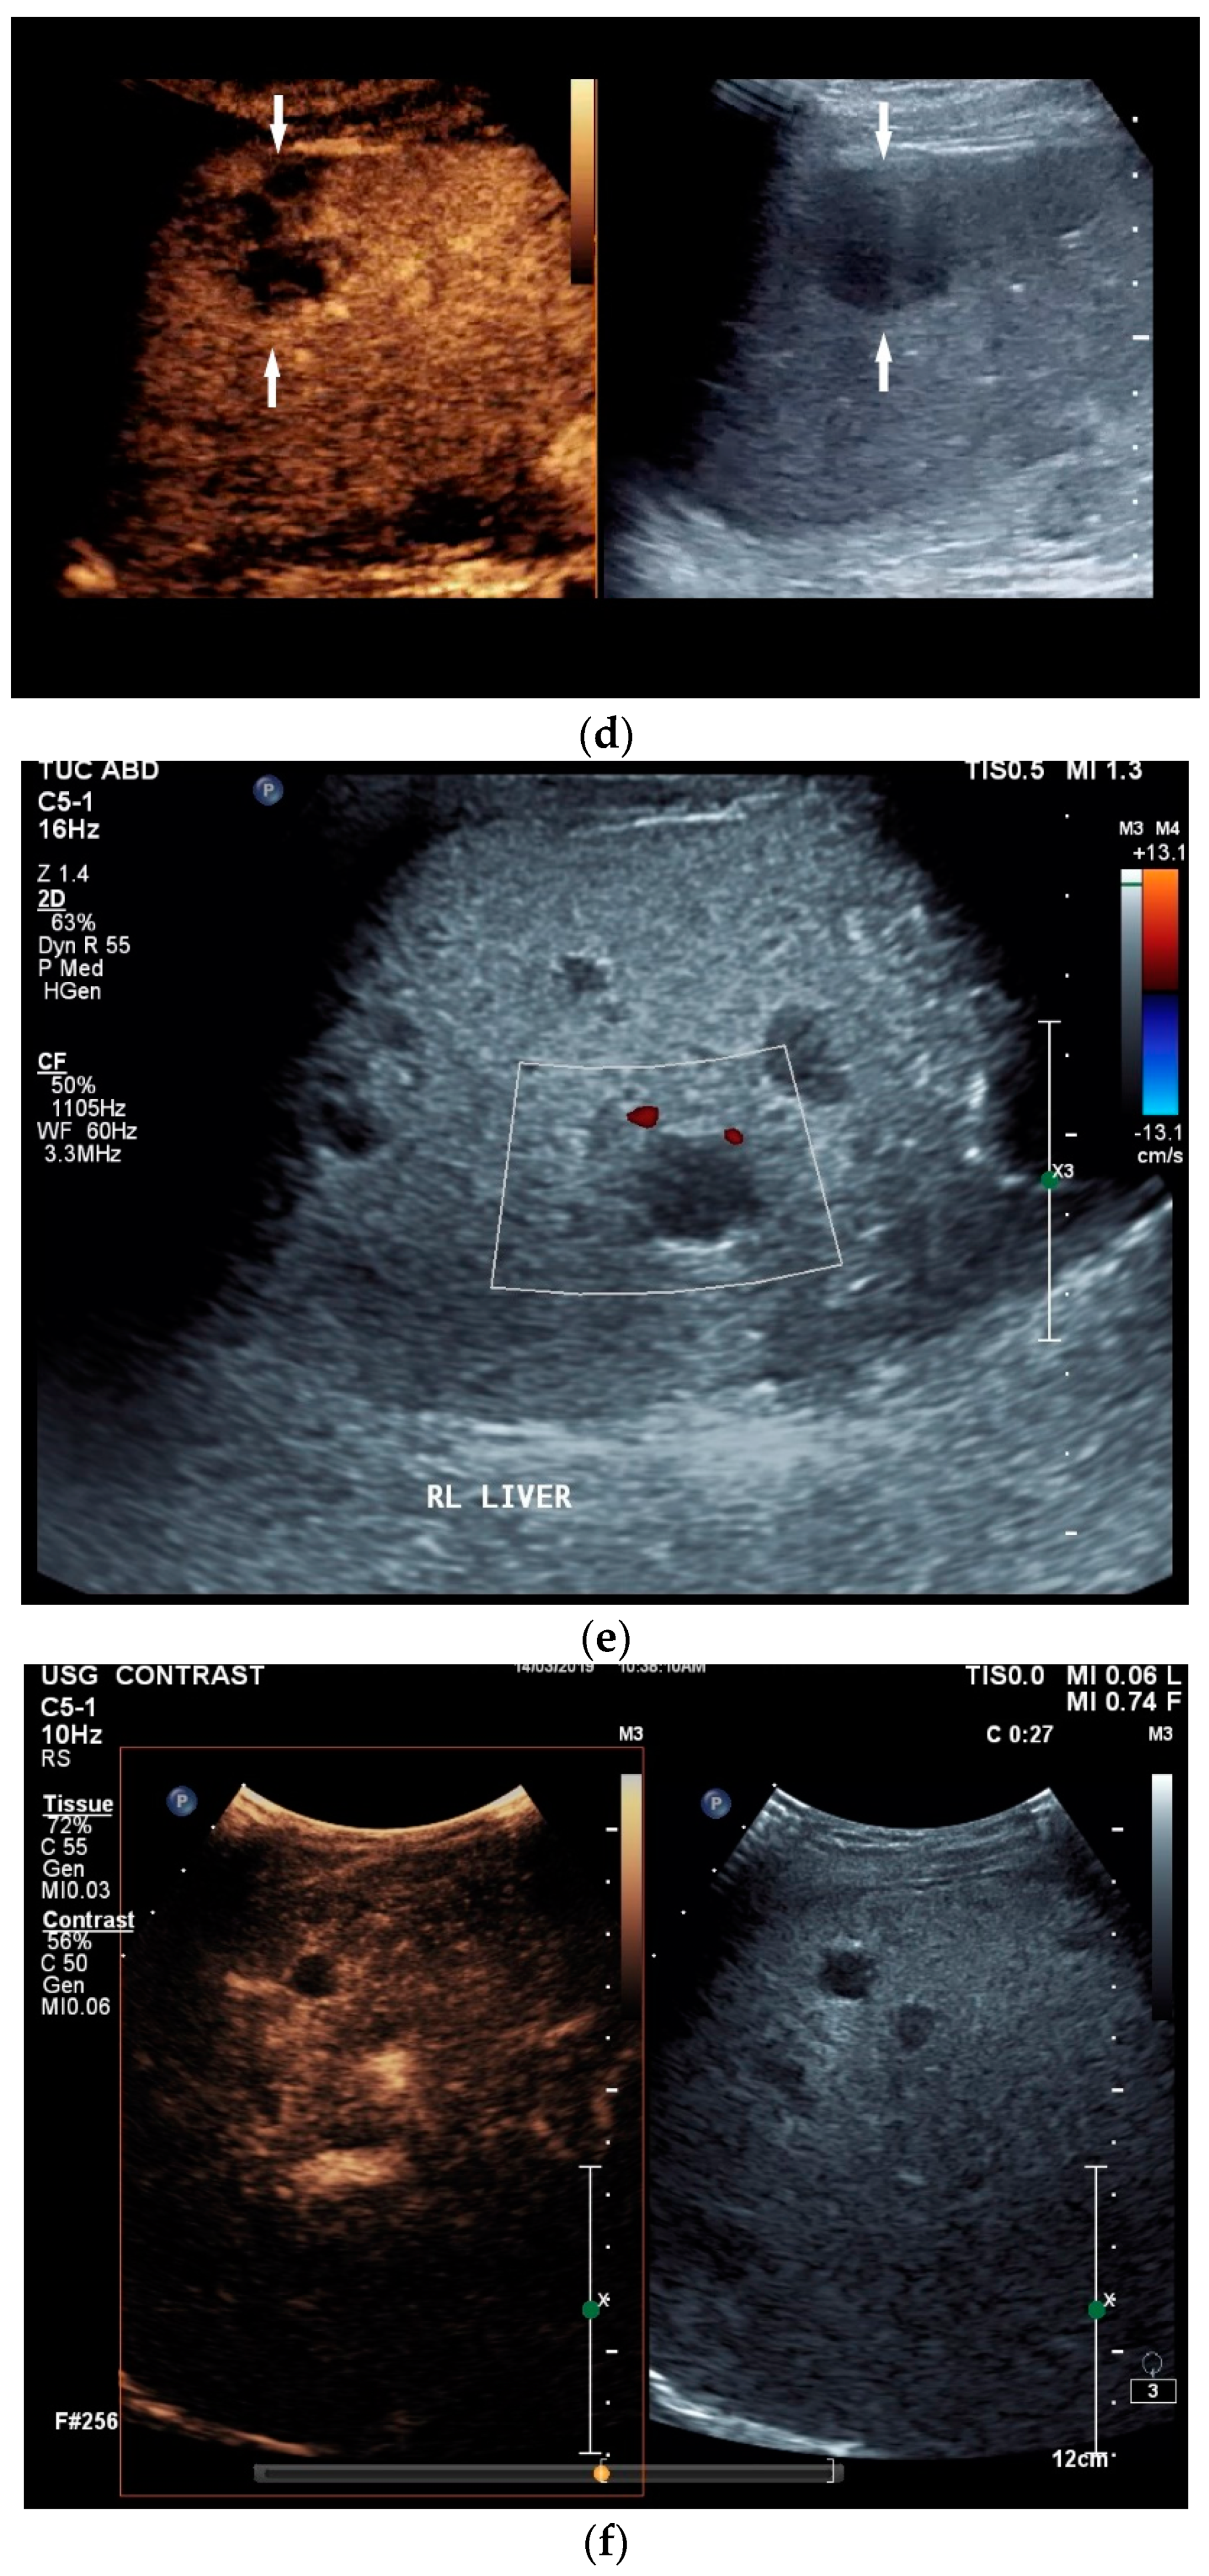

6. Liver

Liver involvement in active tuberculosis is rarely reported, with a frequency of approximately 1% [51,52]. It is more common with concomitant HIV disease at 18% [5,6,52]. Isolated tuberculosis of the liver is very rare, and has been described in just 1% of all cases [53,54]. In an autopsy study of patients with miliary pulmonary tuberculosis, 91% had liver involvement [55]. In the liver, tuberculosis manifests with diffuse- or focal-type nodular lesions. These can be micronodular (miliary) lesions or macronodular lesions [56,57,58]. A third variant is the serohepatic form, with a thickened liver capsule and subcapsular nodular lesions [56] [Figure 3a,b].

Figure 3.

Sonographic and CEUS features of hepatic tuberculosis. Subcapsular liver lesion (a); subcapsular liver lesions (white arrow) and hypoechoic lesion on the capsule (green arrow) using a linear transducer of 12 MHz (b). Caseous necrosis, histologically proven. Hypoechoic lesion with hyperechoic rim using B-mode ultrasound (right side of image). The lesion is hyperenhanced in the arterial phase at the edge of the CEUS; the center is nonenhanced with the exception of some enhanced septa (c). In the portal venous phase, the peripheral areas are hypoenhanced (d). Multiple small, smoothly bordered, non-cystic hypoechoic lesions in the liver, with no evidence of macrovessels when using Color Doppler Imaging (e). CEUS shows mild peripheral enhancement around the lesions. The lesions are without enhancement in the arterial phase (f), portal venous phase (g), and late phase (h).

Abscesses can develop from the caseous necrosis, but are rare [58]. The formation of a multiseptated liver abscess with numerous septa has also been described in a case study [60] [Figure 3c–g].

The morphological correlate of hepatic tuberculosis is granulomatous inflammation, characterized by central caseous necrosis with peripheral granulation tissue. Both melting abscesses and calcified nodules may occur in the course of the disease.

Ultrasound presents hypoechoic or isoechoic liver lesions [56]. Hyperechoic lesions are rarely described (although, these can be found in hepatitis B infections and hepatitis C-related liver cirrhosis; however, histologically confirmed cases have categorized these as tuberculoma related, and not as regenerative nodule or hepatocellular carcinoma (HCC)) [59,61]. Depending on the stage of the disease, the inflammatory lesions are homogeneously hyperenhanced via CEUS. Most lesions develop a washout in the portal venous phase. Melting abscesses show a hyperenhanced rim with either a hypoenhanced or nonenhanced center or a heterogeneous enhancement [62,63] [Figure 3c,d]. Vascular complications, such as portal vein thrombosis, have been caustically described and found to be in connection with hepatitis B [54,64].